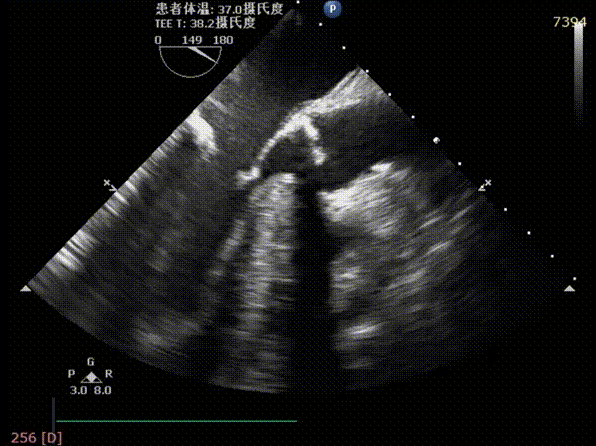

术前TEE评估主动脉瓣

释放后超声评估

释放后超声下多切面评估,瓣膜位置可,无明显瓣周漏

测得主动脉瓣流速由5.4m/s改善至1.9m/s